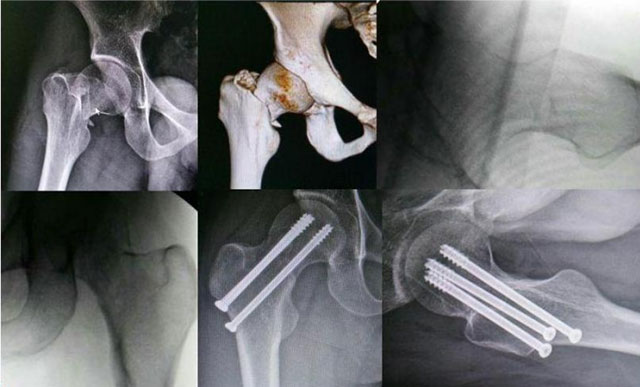

保守治疗效果不佳最终骨坏死

三枚螺钉固定

动力髋螺钉固定

骨折内固定:可以予以骨折内固定术。如三枚螺钉固定、动力髋螺钉固定。

通俗来讲就是固定两端股骨头和股骨,避免其再次移位,然后慢慢等待骨折愈合。